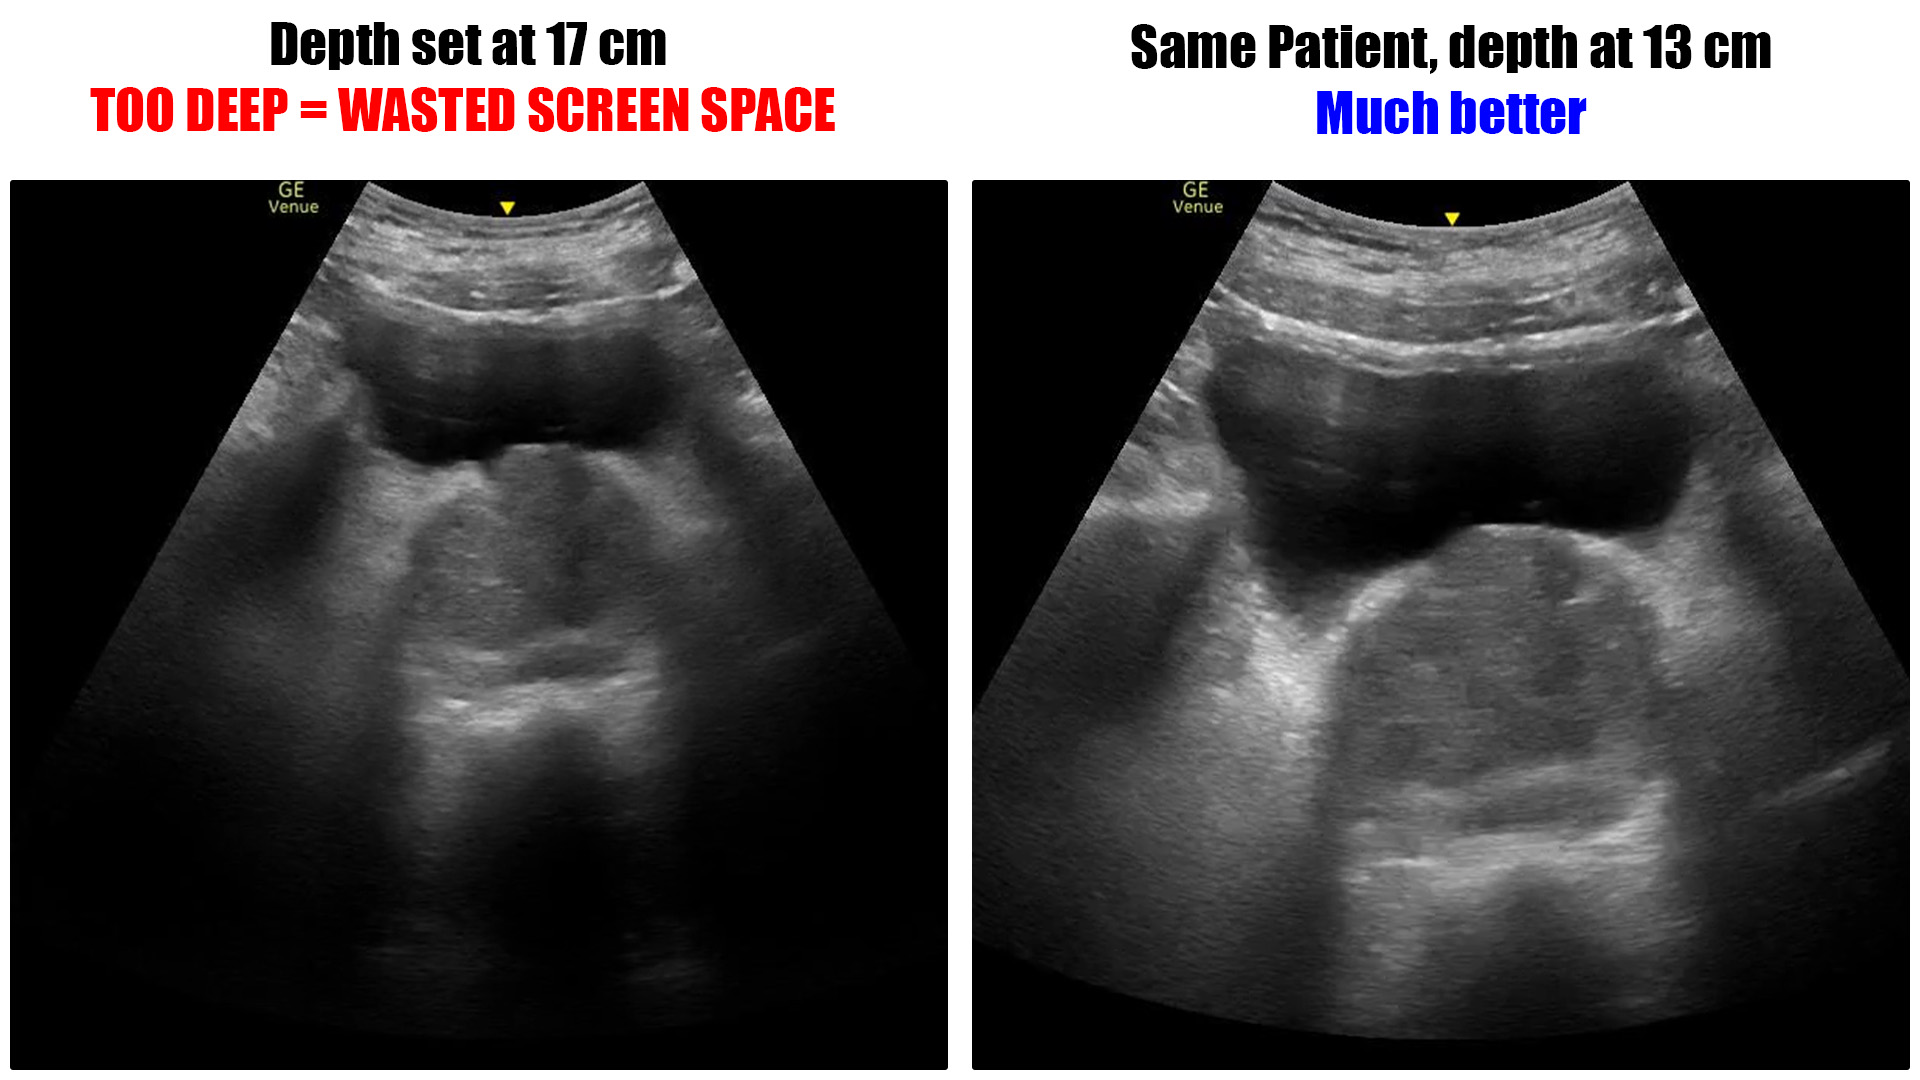

Discussions about depth bring up the concept of the “area of interest” or “AOI”. The AOI is whatever it is that you are looking for on that particular study. Maybe it’s the heart or the gall bladder or the pleural line, for example. You want your depth setting to be such that the AOI takes up as much room on the screen as possible while being able to see something around it for context.

Too much depth

The problem with too much depth is that it wastes screen space. The machine has to use computing power to fill every pixel on the image. Every pixel that is used for something other than the AOI is wasted space. That means less of the screen is filled by the area of interest.

In general, it would be a good practice to set your depth such that the deepest edge of the AOI is about 3/4 of way down the image. That gives you a look at the entire organ in question and leaves some room at the deepest part of the image for context without “cutting it close.”